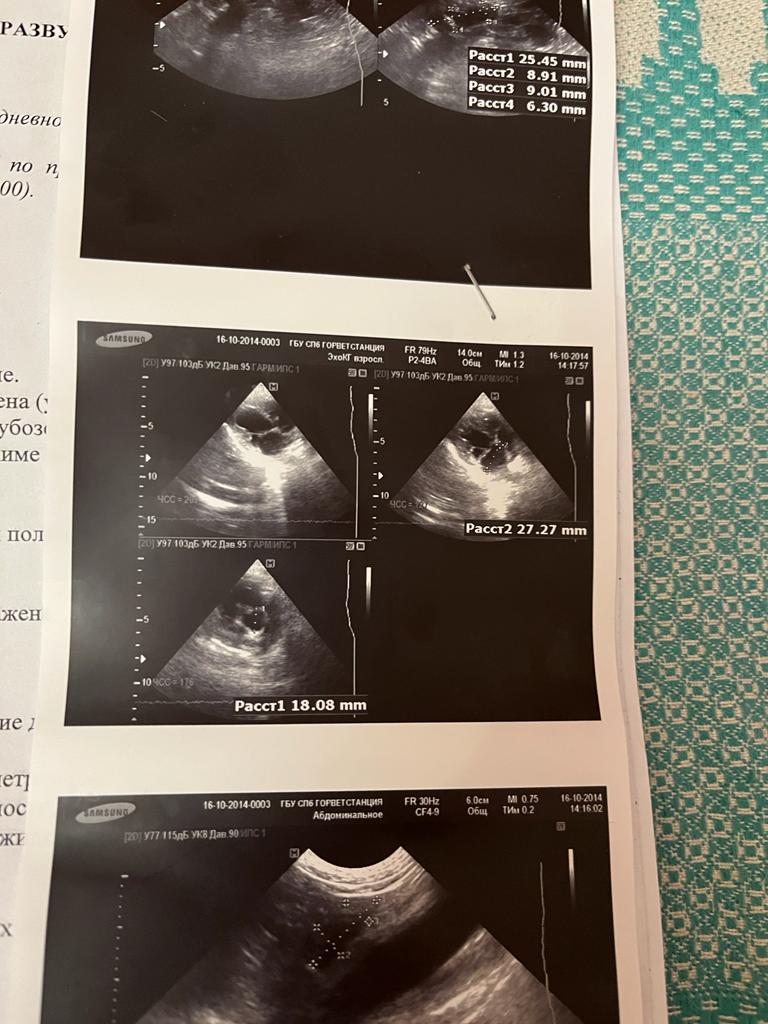

Спб, метис цверга Дара, 8-9 лет

Послеоперационная выписка